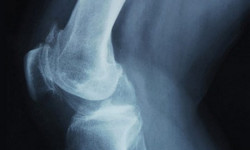

The sound your knee makes is somewhere between a crack and a pop. Anything more than that may mean your knee is broken. For many athletes, knee popping may be part of warm up exercises, but they don’t do it for its own sake. Common reasons of knee popping Again, the knee popping sound here is not meant for laughs. It happens at a time you’re not ready for it, […]